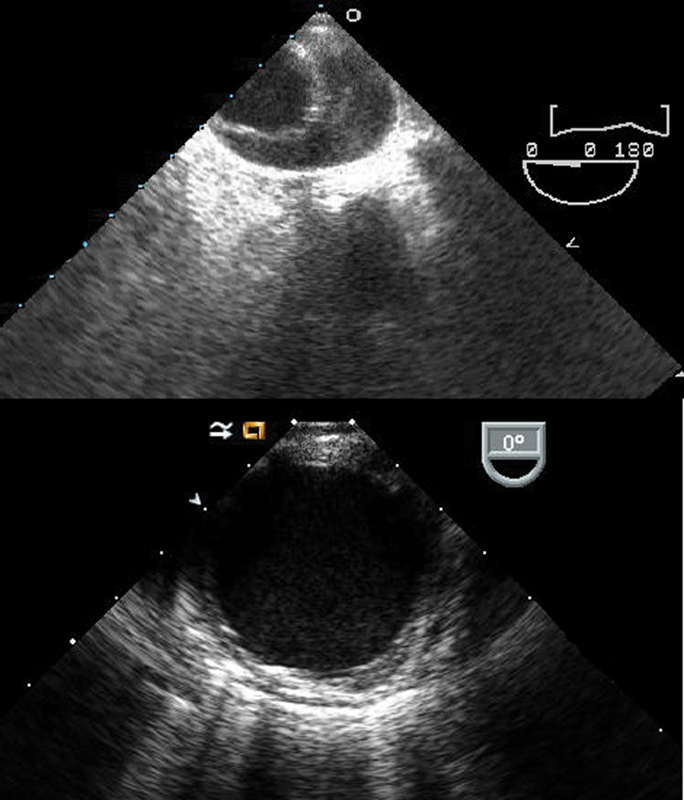

فحوصات تشخيصية لبعض امراض القلب والشرايين التاجية